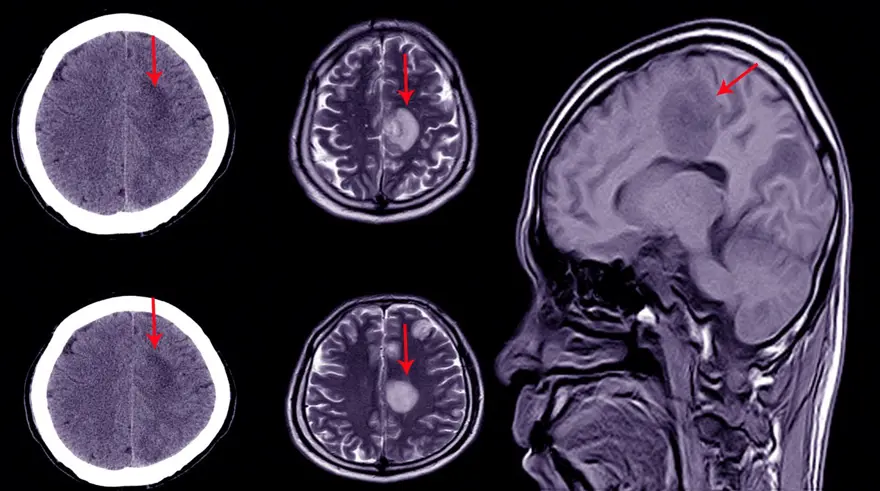

Diğer taraftan, Frontiers in Cellular Neuroscience adlı bilimsel dergide yayımlanan yeni çalışma, insanlarda ve farelerde nöronlar arasındaki dopamin ile güçlendirilmiş bağlantılara odaklandı ve ödülle ilişkili nörotransmiterin insan beynindeki nöronlar arasındaki bağlantıları güçlendirdiğini gösterdi.

Louth'a göre bunu bilmek, örneğin felç veya diğer akut beyin hasarı türlerinden sonra rehabilitasyonla bağlantılı olarak, hastaların beyindeki sinaptik bağlantılarını kaybettiği ve yenilerini oluşturması gerektiği durumlarda, yeni tedavi fırsatlarına yol açabilir.

Louth, "Bize dopaminin insanlarda ve farelerde farklı bir rol oynadığını gösterme fırsatı verildi. Bu, bir ilacın veya bir nörotransmitterin etkisinin türler arasında nasıl değiştiğine dair gerçekten iyi bir örnek ve ilaçları doğrudan insan dokusu üzerinde test edebilmenin önemini vurguluyor” değerlendirmesinde bulundu.